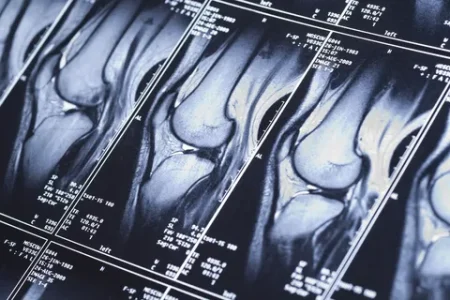

МРТ коленного сустава — самый информативный способ увидеть внутри структуры, которые недоступны обычному осмотру или рентгену. Статья расскажет, в каких ситуациях томография действительно нужна, как проходит процедура, что врач видит на снимках и как трактовать результаты. Также узнать больше можно на сайте https://spb.ramsaydiagnostics.ru/mrt/mrt-sustavov/mrt-kolennogo-sustava/

Томография отображает мениски, переднюю и заднюю крестообразные связки, медиальные и латеральные структуры, суставной хрящ и кости. Это помогает диагностировать разрывы, отёк, хондропатию и опухолевые процессы на ранней стадии.